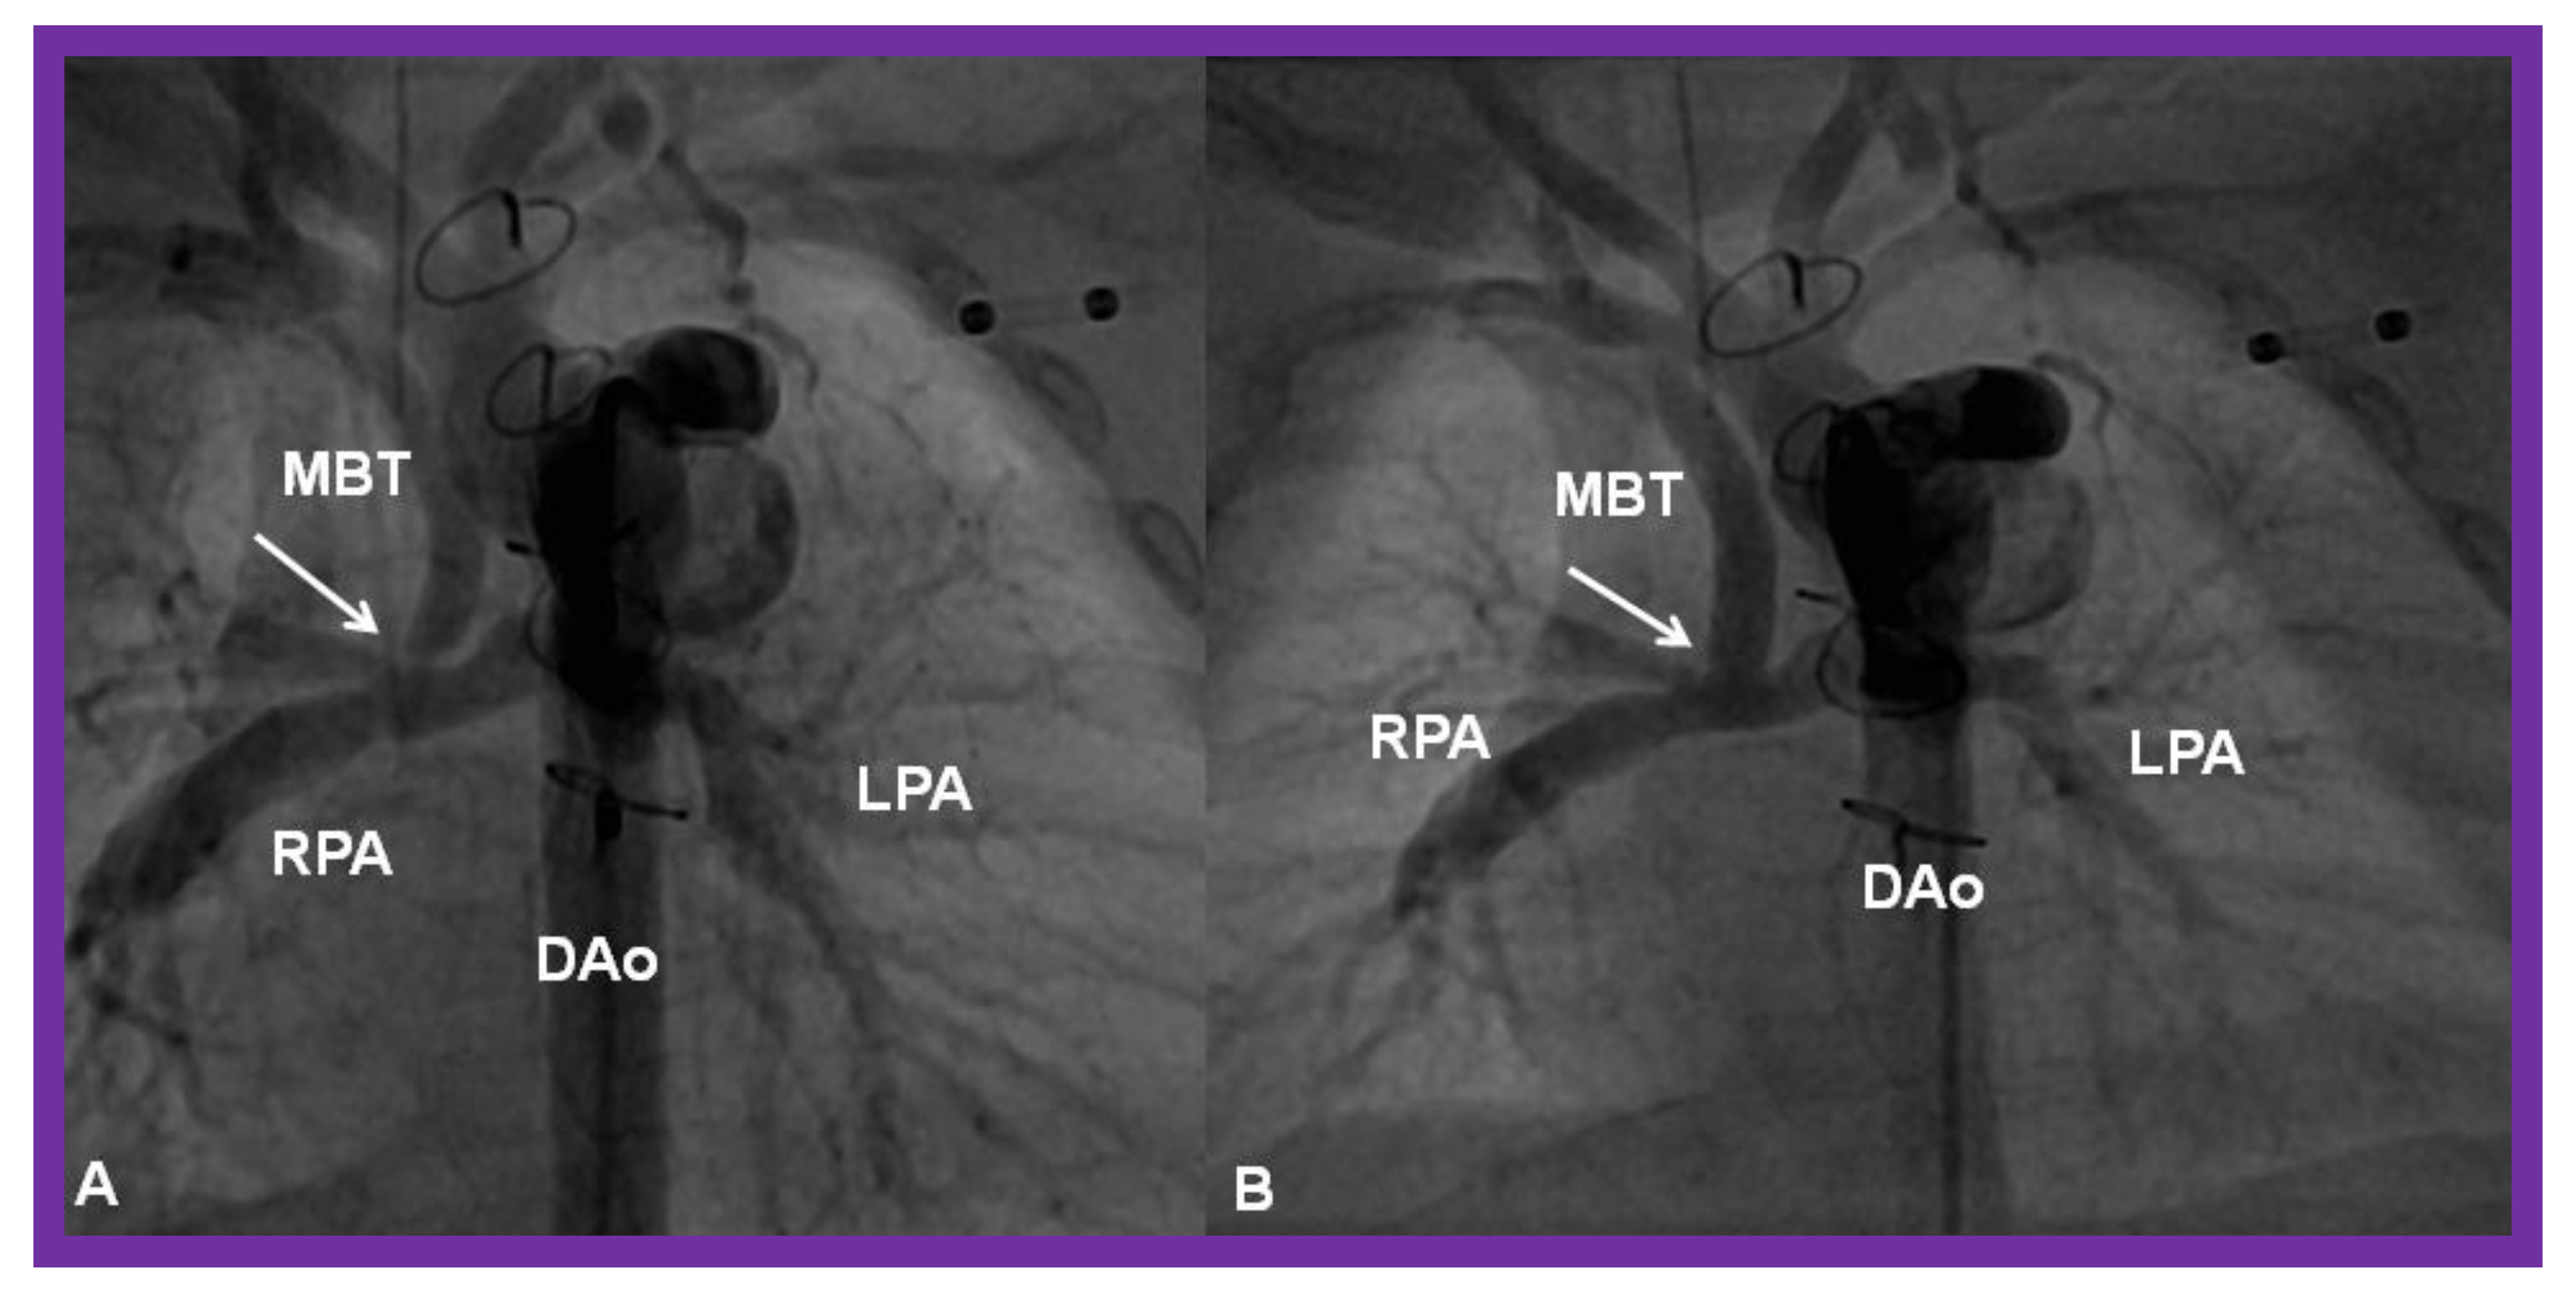

Figure 28.

(A) Selected cine frame in a postero-anterior view, demonstrating discrete narrowing (arrow) of a modified Blalock-Taussig (MBT) shunt. (B). Following stent implantation, this site is wide open (arrow in (B)). DAo, descending aorta; LPA, left pulmonary artery; RPA, right pulmonary artery. Reproduced from Reference [58].